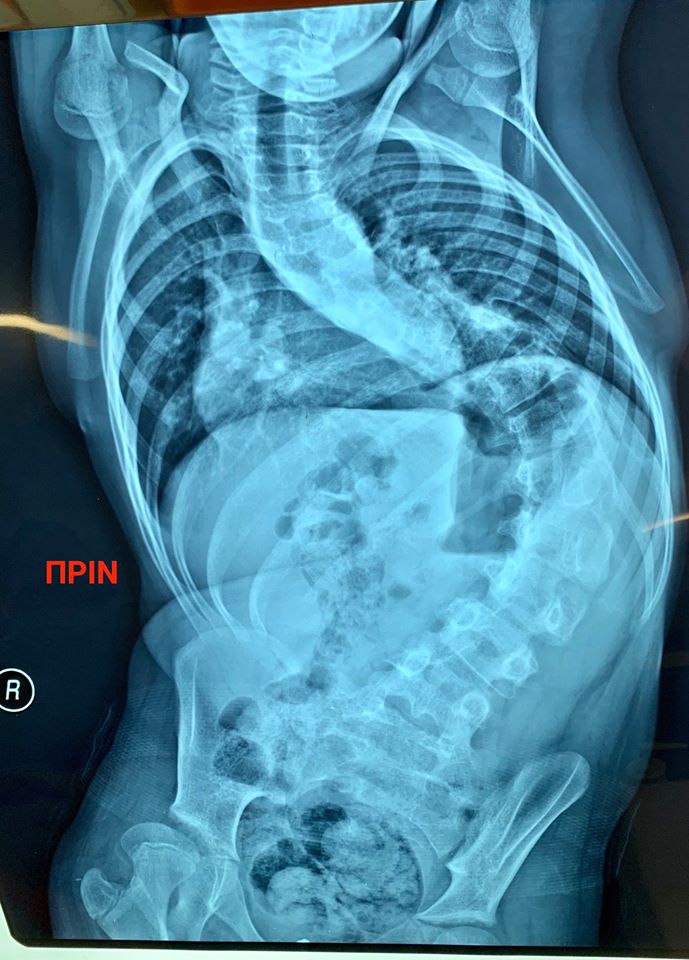

Αμέτρητοι είναι οι φίλοι που μας ευχήθηκαν και μας έδωσαν κουράγιο σε μια δύσκολη περίοδο για το Γιαννάκη μας. Ήταν ο μήνας που έπρεπε επιτέλους να μπούμε στο χειρουργείο για ολική σπονδυλοδεσία. Λόγω της προχωρημένης και ιδιότυπης σκολίωσης τα πράγματα ήταν εξαιρετικά δύσκολα και ειδικά για ένα παιδί ΑΜΕΑ με βεβαρημένο ιατρικό ιστορικό.